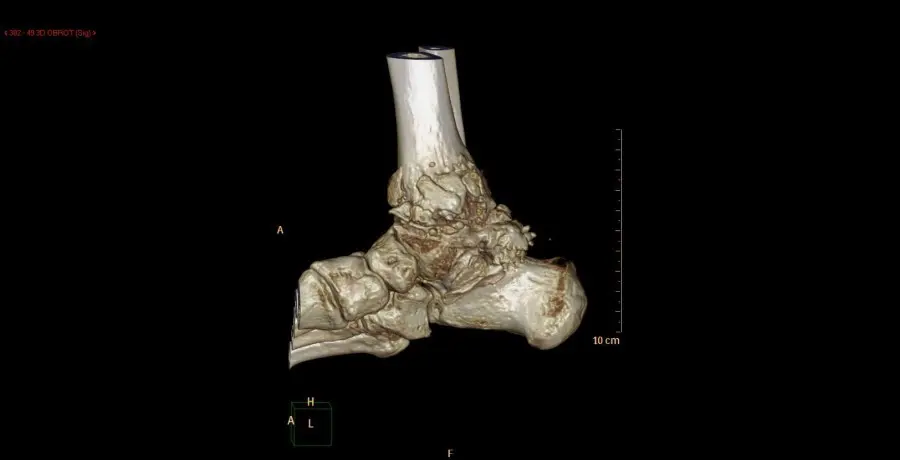

Rekonstrukcja 3D w tomografii komputerowej artrotycznego stawu skokowego Rekonstrukcja 3D w tomografii komputerowej artrotycznego stawu skokowego